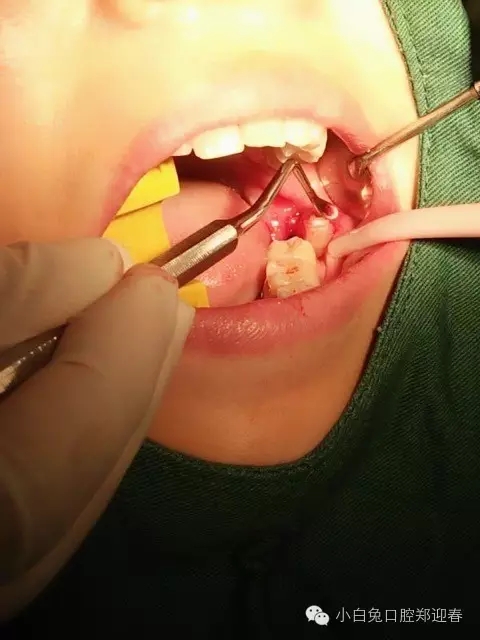

病例介紹:患者,女,37歲,要求拔除智齒斷根,1個半月前,因左下智齒拔除,術(shù)中因斷根取出未果而中斷拔牙,但術(shù)后一直不舒服,今來診要求拔除剩余一例智齒斷根二次拔除的感悟

使用微創(chuàng)理念及方法繼續(xù)拔除剩余部分

很得力的4號微創(chuàng)牙挺

來自小白兔口腔鄭迎春